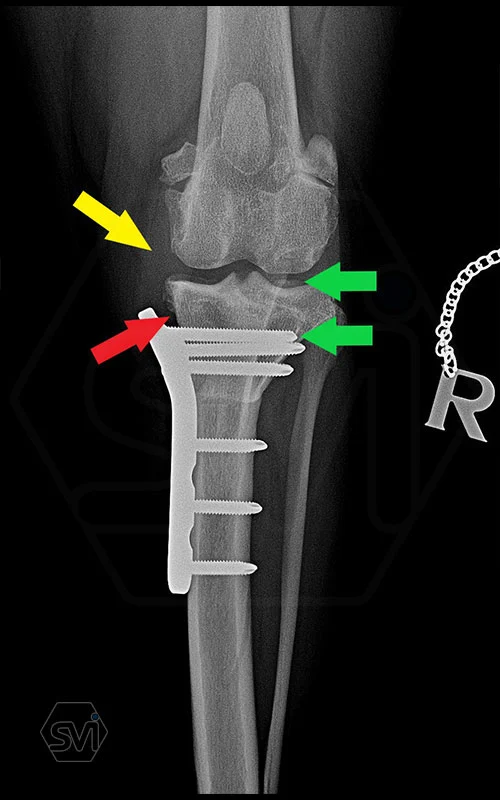

In the picture, the thickend med. collat. lig. marked with a yellow arrow, and the plate follows its shape, marked with a red arrow. The blood circulation in the tissues under the metal is not disturbed, which does not generate further pain and results faster bonehealing.

The screws were inserted in the proximal part with the monoaxial drill guide so the screws were parallel to the tibial plateau and we were sure during surgery that the screw would not penetrate the joint and the screw head would fit into the hole with maximum surface area!